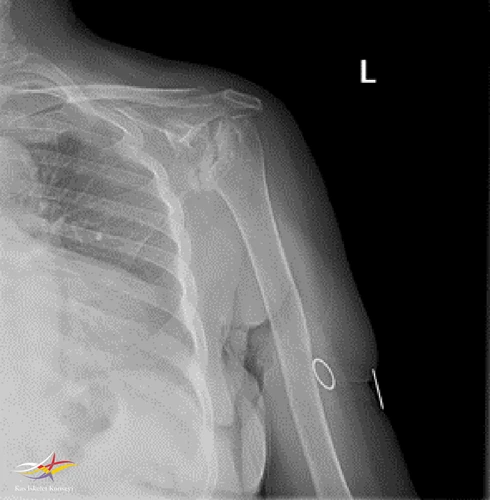

Resim 2. Sol omuz direkt grafi-2.

Sol Omuz MRG: Glenoidde kortikal düzensizlikler, lokalize defektif alanlar ve bu düzeyde subkondral milimetrik kistlerin eşlik ettiği medüller hafif hiperintens ödem izlenmektedir. Humerus baş kesiminde medialde de geniş bir alanda defektif görünüm mevcuttur. Buna komşu humerus başında milimetrik kistler ve medüller ödem izlenmektedir.

Humerus başında ve glenoid de osteofitik dejeneratif değişiklikler mevcuttur. Gleno-humeral eklem aralığı anterior inferiorda daralmıştır.Eklem aralığında sıvı miktarında belirgin artış izlenmedi.

Humerusta tüberkülüm majusta milimetrik kist - medüller ödem benzeri sinyal değişikliği dikkati çekmektedir.

Akromioklaviküler eklemde minimal dejeneratif hipertrofi izlenmekte olup eklem aralığı yaklaşık 5 mm ölçülmüştür ve normal sınırlar içerisindedir. Subakromial yağ mesafesi basılıdır. Akromion Tip 2 konfigürasyondadır. Glenoid labrumlar değerlendirilemedi. Biceps uzun başı tendonu normaldir. Supraspinatus tendonunda tendinozis izlenmektedir.